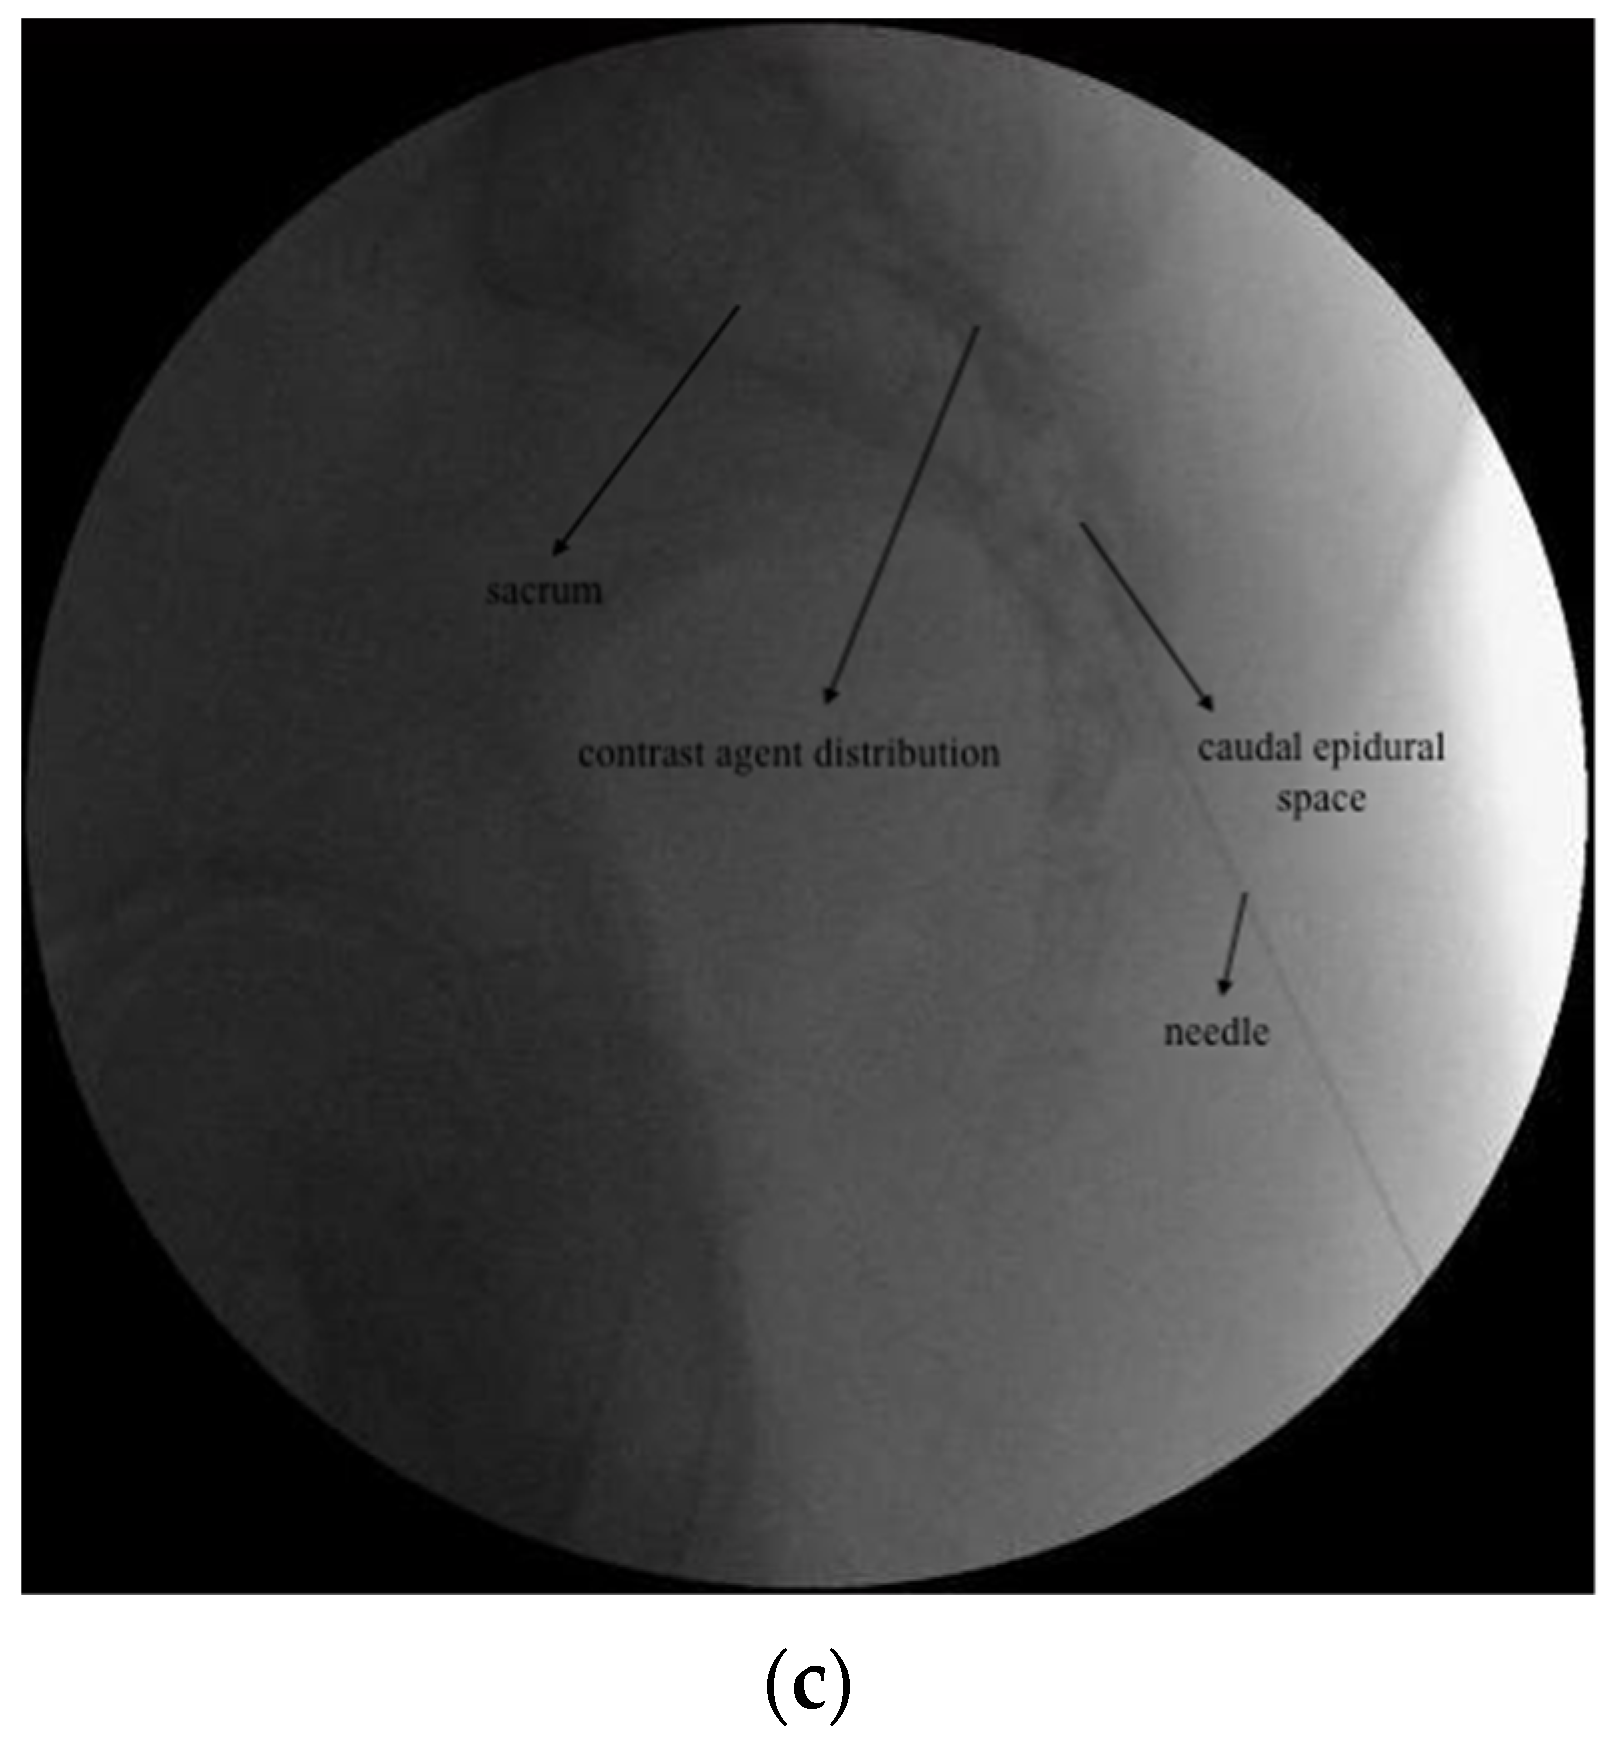

(a): DRG PRF fluoroscopic image; (b): TESI fluoroscopic image; (c) CESI fluoroscopic image.

2.3.2. CESI

Under fluoroscopic guidance, the caudal epidural space was visualized in the lateral view. Following skin infiltration with 1 mL 2% lidocaine, a 22-gauge spinal needle was advanced to the caudal epidural space. After visualizing appropriate contrast distribution, a total of 10 mL (40 mg/1 mL methylprednisolone acetate and 9 mL 0.9% NaCl) was injected (Figure 1c).